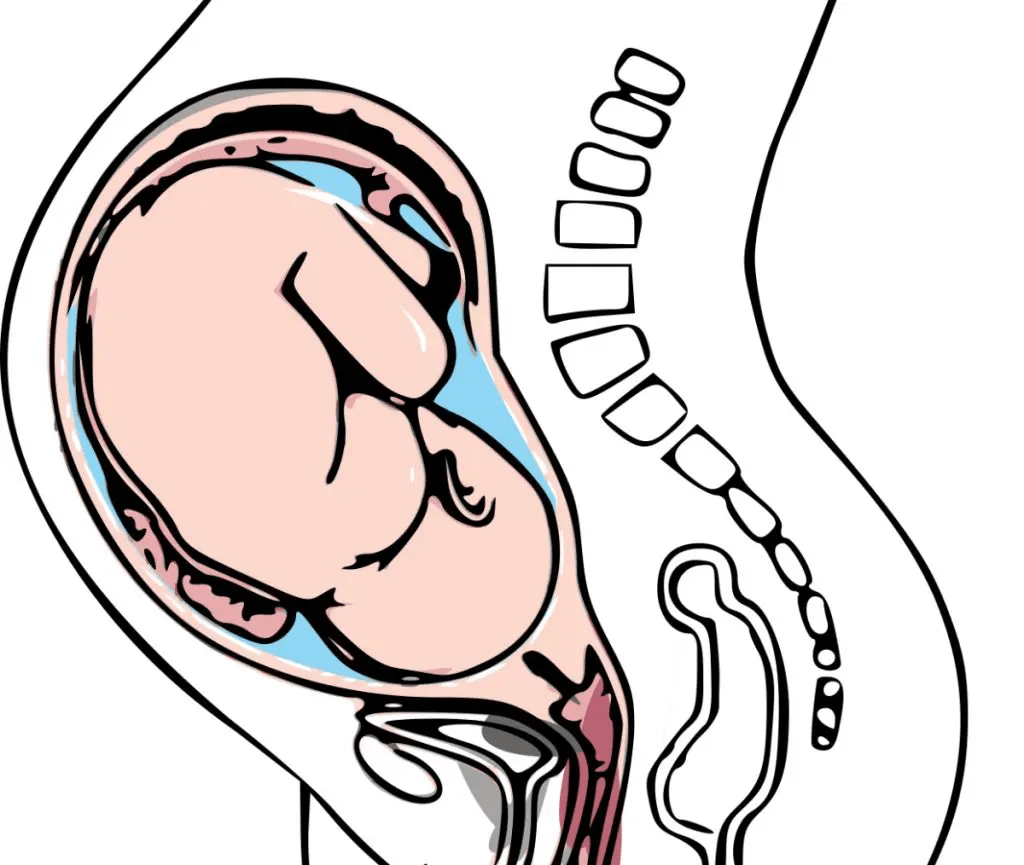

Ačkoli není výskyt spina bifida aperta plodu častý, jedná se o velký problém, který je viditelný již na ultrazvuku prováděném při kontrolách těhotných. Při této vrozené rozštěpové vadě nedochází během nitroděložního vývoje plodu k uzavření nervové trubice a páteře. Mohou tak vyhřezávat jak míšní obaly, tak mícha a dochází k jejímu poškození. Po porodu je nutné novorozence operovat. Vědce napadlo, že by mohly pomoci kmenové buňky, pokud by se aplikovaly do dutiny s plodovou vodou (intraamniálně). Svou domněnku ověřovali na krysím modelu. Využili k tomu kmenové buňky z kostní dřeně, které nejprve kultivovali s nervovým růstovým faktorem a aplikovali je do amniové dutiny. Kmenové buňky se přemístily do oblasti poškození, kde zvýšily produkci nervového růstového faktoru v poškozené míše. Diferencovaly se do neuronů a buněk podobných kožním a jejich působení vedlo ke zmenšení oblasti poškození a zlepšení stavu míchy.

Je možné, že by z takové léčby mohly mít prospěch také děti, které trpí spina bifida aperta. Cesta k zavedení této léčby však bude ještě dlouhá.